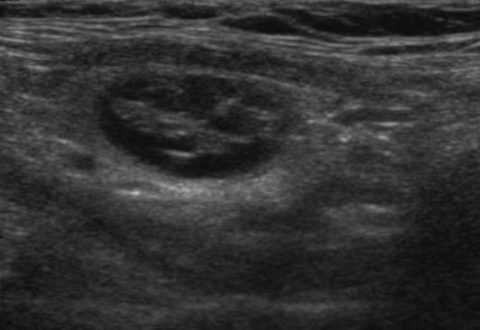

Узлы коллоидного типа, как правило, не представляют опасности для жизни человека, кроме случаев, когда эти новообразования разрастаются до таких размеров, что начинают давить на окружающие важные для жизни анатомические структуры. В таких новообразованиях усиление кровотока наблюдается только по их краям (ободках). Эти особенности указывают на то, что вокруг узла имеется капсула.

Коллоидный узел при ультразвуковом исследовании

Согласно статистическим данным, периферийная васкуляризация характерна для доброкачественных новообразований (до 85% узлов с таким типом кровоснабжения). Как правило, это капсулы с наполнением в виде гелеобразного коллоида либо жидкости.

Новообразование в щитовидке с перинодулярным кровотоком

Однако отмечаются весьма редкие случаи, когда перинодулярный кровоток узла щитовидной железы наблюдается при злокачественных новообразованиях, проходящих ранние этапы своего развития, до начала процесса ангиогенеза.

Интересно! И в том, и в другом случае, новообразования будут давать гипоэхогенную картину, поскольку их внутреннее содержимое, — жидкостное.